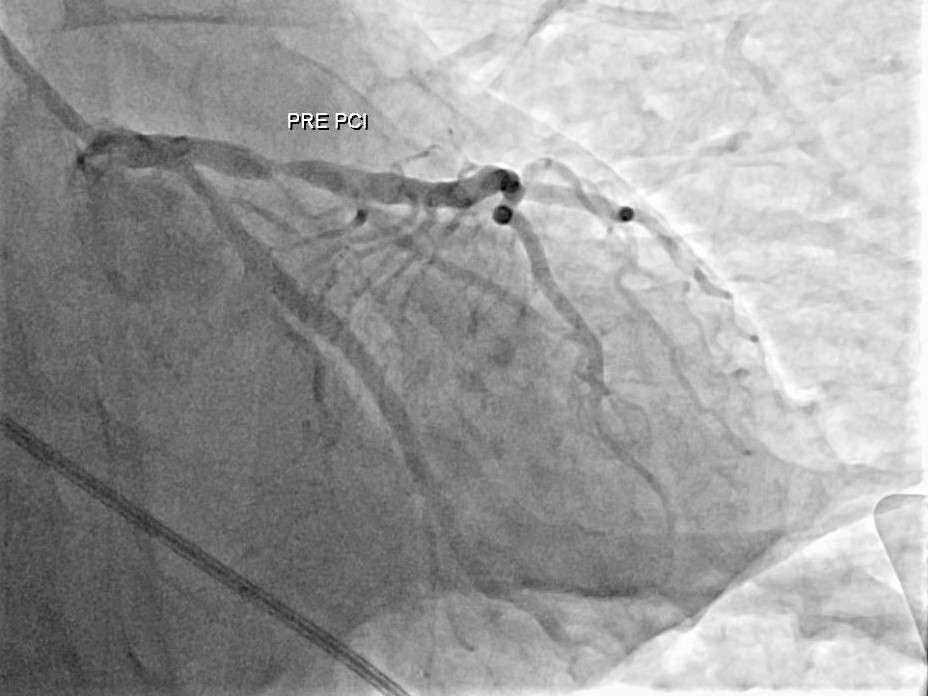

急診醫護團隊第一時間施行高品質心肺復甦術(CPR)、電擊除顫及氣管插管等緊急處置,成功讓患者恢復自主心跳,並迅速轉入心導管室,由心臟內科羅勖中醫師緊急接手治療。經心導管檢查發現,患者左前降支(LAD)幾乎完全阻塞,為典型導致猝死的致命型心肌梗塞。羅醫師果斷進行冠狀動脈介入治療,於極短時間內開通阻塞血管並植入支架,有效恢復心肌灌流,爭取到救命的黃金時間。